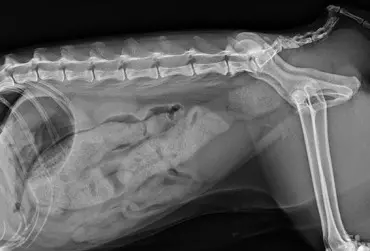

Zarażenie psa pasożytem nicieniem Dirofilaria immitis – opis przypadku

W artykule opisano przypadek dirofilariozy u psa wywołanej D. immitis. U badanego pacjenta stwierdzono patognomiczny obraz zmian w badaniu rentgenowskim i ultrasonograficznym układu sercowo-naczyniowego.